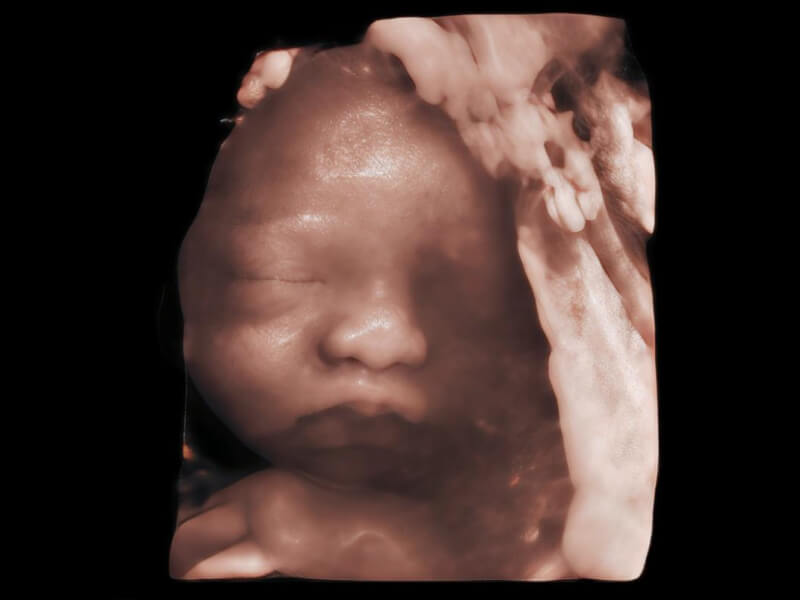

夢(mèng)溪?P80以“關(guān)愛(ài)女性”為基石,提供全方位的解決方案,量身定制以滿足女性的健康需求,涵蓋婦科、生殖健康檢查、產(chǎn)前篩查及產(chǎn)后康復(fù)等領(lǐng)域。